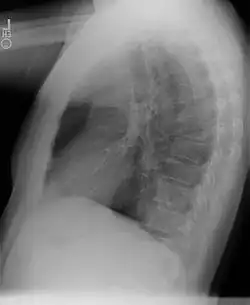

La tomodensitométrie thoracique, avec injection de produit de contraste iodé, permet généralement d'évoquer le diagnostic.